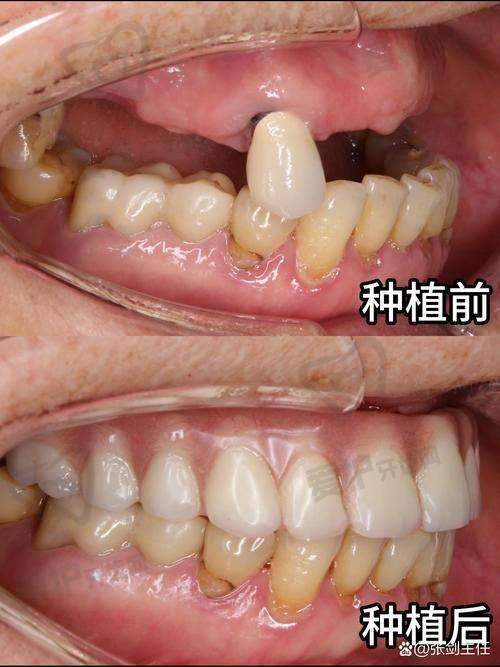

广州曙光美云口腔美国皓圣种植牙的成效如何?

从众多患者的反馈来看,广州曙光美云口腔牟家云医生做的美国皓圣种植牙成效非常好。种植牙的稳定性高,能够像真牙一样正常咀嚼食物,修复了患者的咀嚼功能。而且种植牙的外观与真牙非常相似,几乎可以达到以假乱真的成效,不会影响患者的美观。在长期使用过程中,美国皓圣种植牙的使用寿命也比较长,只要患者注意口腔护理,定期到医院进行复查,种植牙可以陪伴患者特别多年。